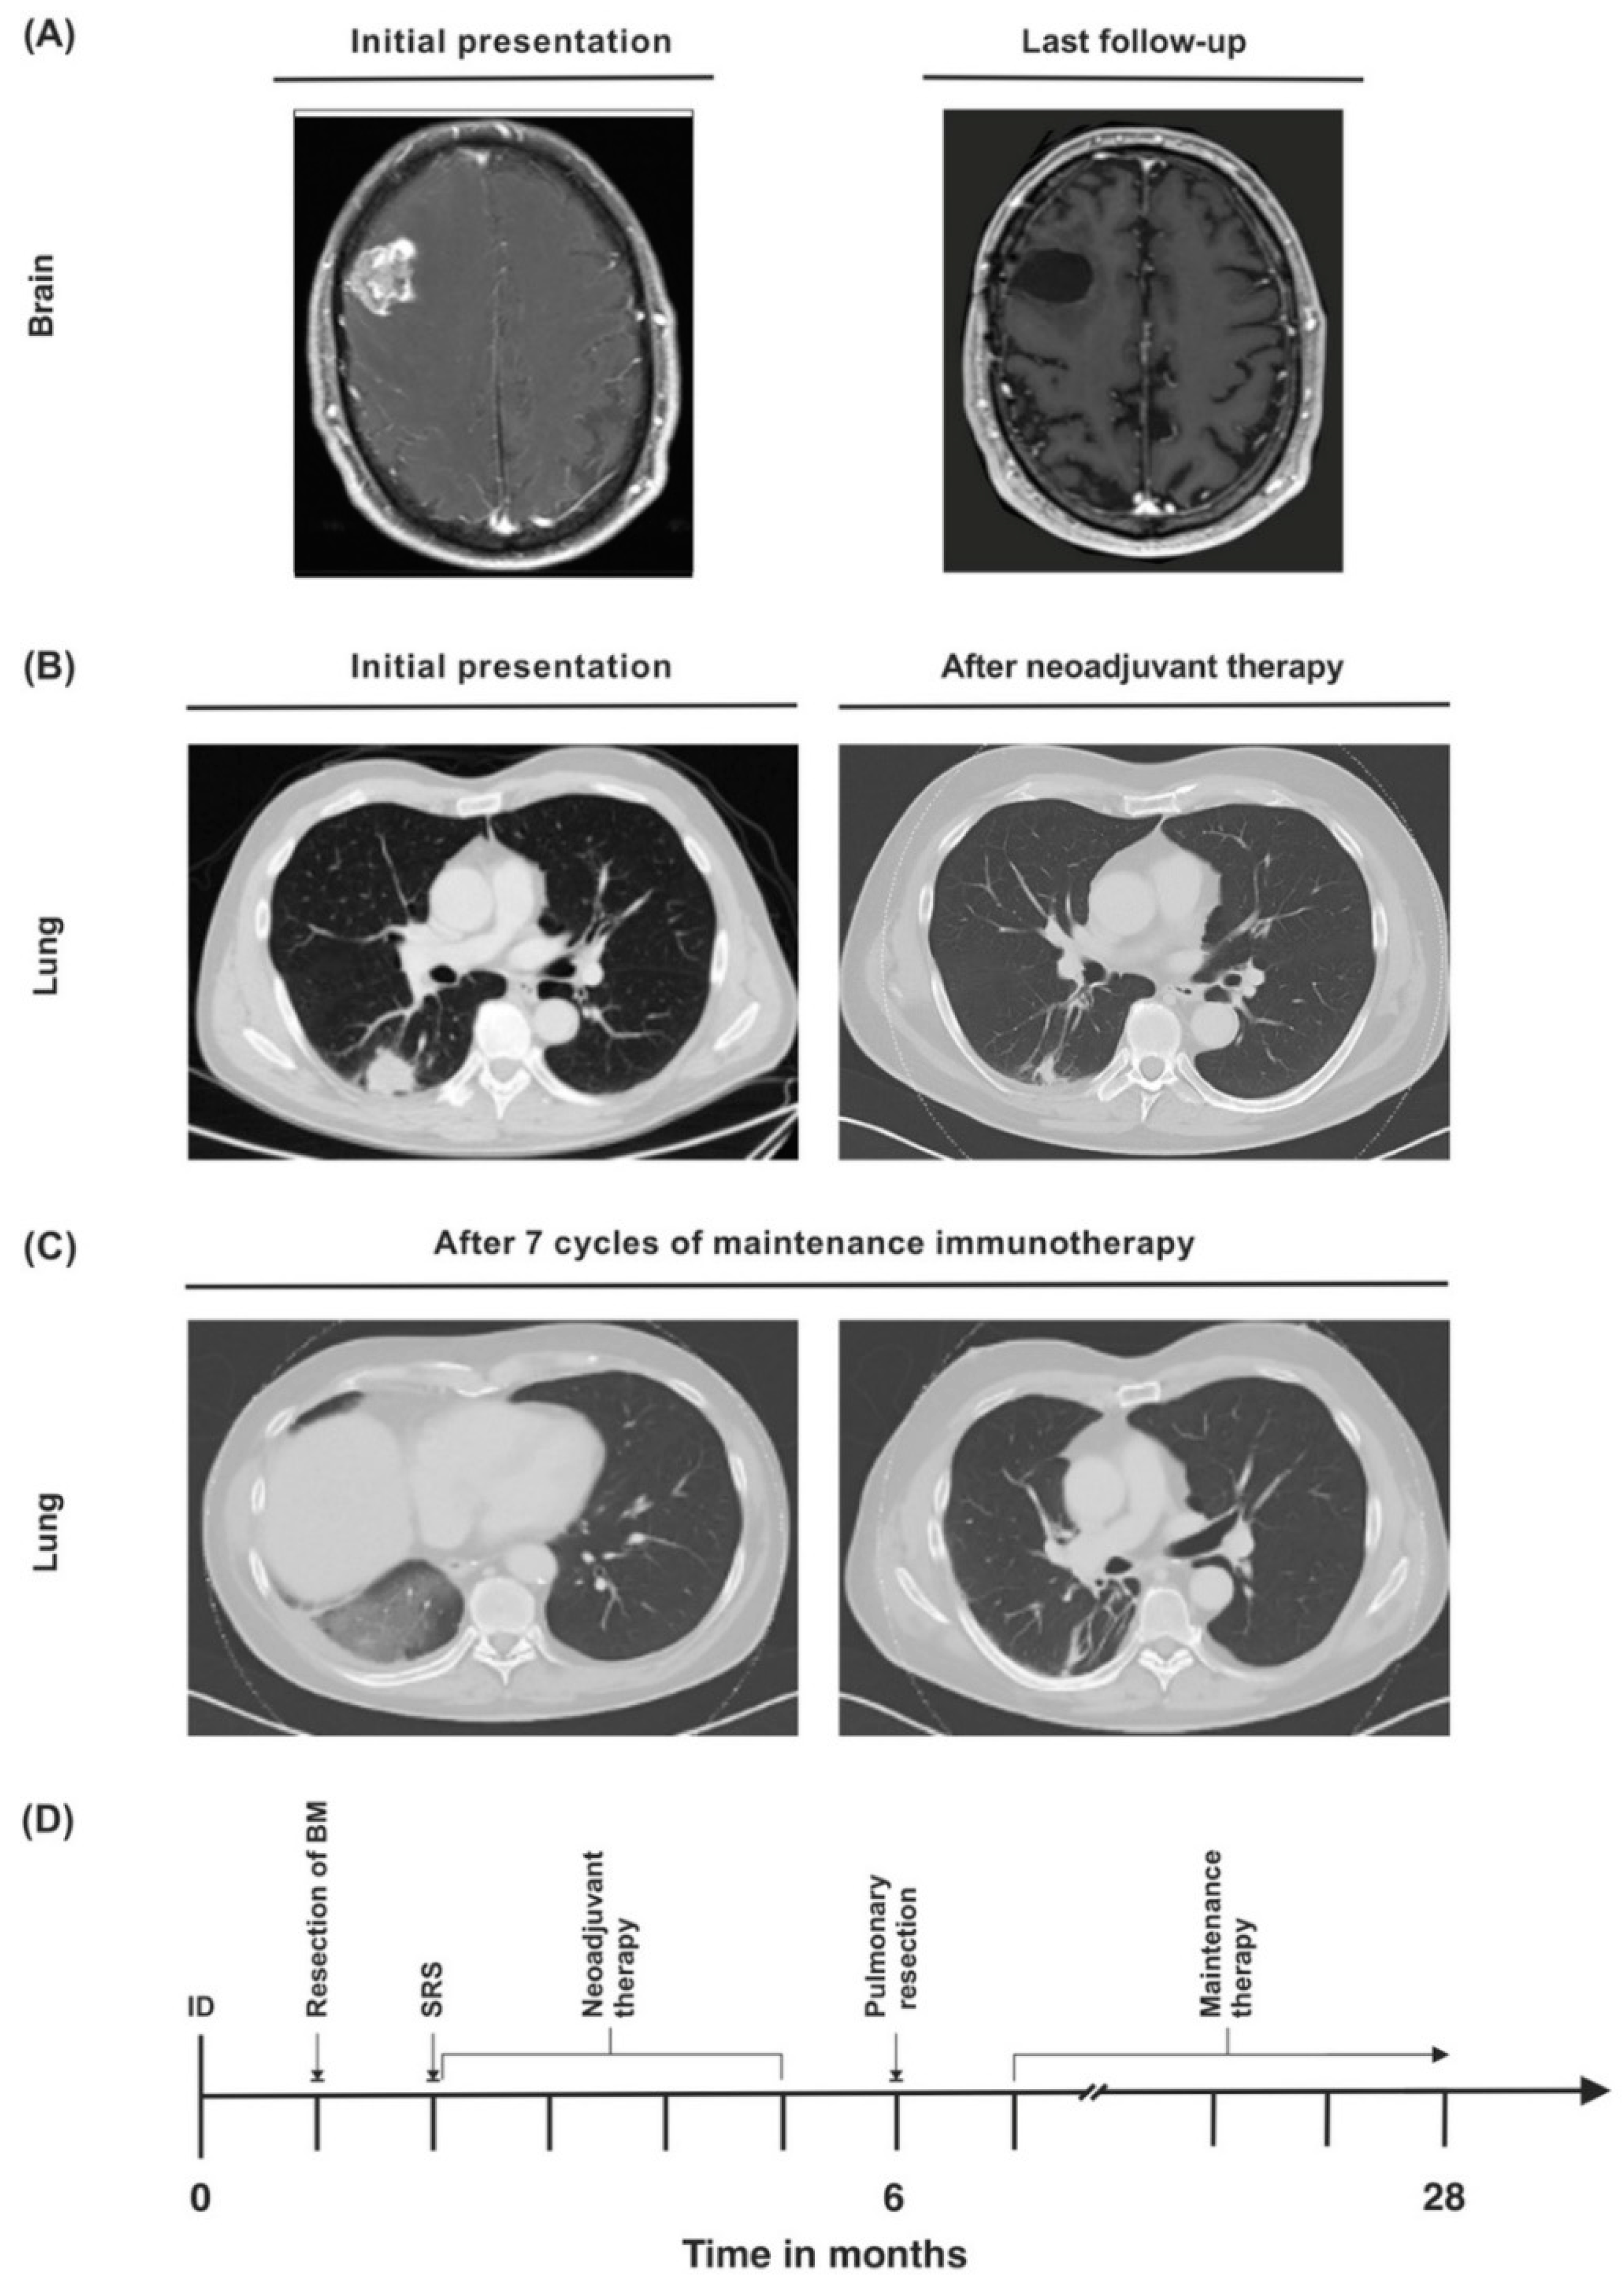

3.1. Case 1

| Treatment of BM | Neurosurgery and SRS | Neurosurgery and SRS | SRS |

| BM radiation dose | 21 Gy | Synchronous BM: 21 Gy, metachronous BM: 20 Gy | 19 Gy |

| Neoadjuvant therapy | Cisplatin (75 mg/m2), pemetrexed (500 mg/m2), and pembrolizumab (200 mg) | Cisplatin (75 mg/m2), pemetrexed (500 mg/m2), and pembrolizumab (200 mg) (+2 cycles of pembrolizumab as maintenance therapy) | Cisplatin (75 mg/m2), pemetrexed (500 mg/m2), and pembrolizumab (200 mg) |

| Pulmonary resection | Posterolateral thoracotomy, subsegment S1-resection, right lower lobe resection, systematic lymph node dissection | Posterolateral thoracotomy, extrapleural extended upper lobectomy, wedge resections (S1, S5, S6), systematic lymph node dissection | Posterolateral thoracotomy, extended left lower lobe resection, wedge resection S1, systematic lymph node dissection |

| Tumor stage after lung resection | ypT0 ypN0 (0/42), L0, V0, R0, Gx, pM1b (BRA), UICC IVA | ypT2b ypN0 (0/22), L0, V0, Pn0, R0, Gx, pM1b (BRA), UICC IVA | ypT2a ypN3 (5/23), L1, V1, Pn0, R0, cM1c (BRA), UICC IVB |

| Maintenance therapy | 200 mg per cycle (ongoing) | 200 mg per cycle (discontinued after 2 cycles because of progressive disease) | 200 mg per cycle (finished after 24 months) |

| Current Karnofsky performance index | 100% | 0% | 100% |